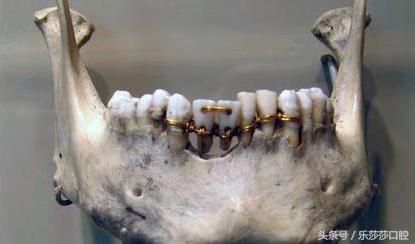

十三、古代的牙齿矫正方法:不止现代人追求「牙齿整齐」,就算在古代也是如此,考古学家发现公元前2500年埃及木乃伊上的「牙科手术」。